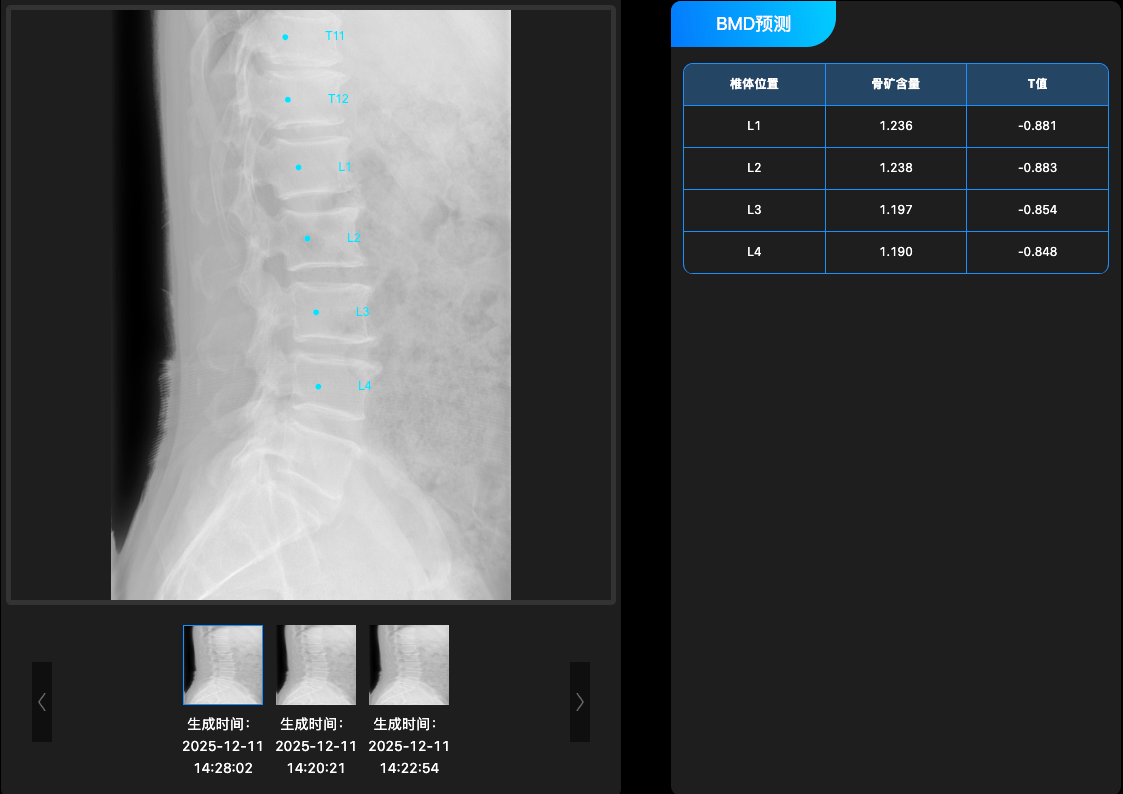

骨密度预测系统

深度融合椎体X线侧位片、体征与病史等多模态数据,通过深度学习算法构建预测模型,无需DXA设备即可实现个体骨密度的精准预测与骨质疏松风险评估。